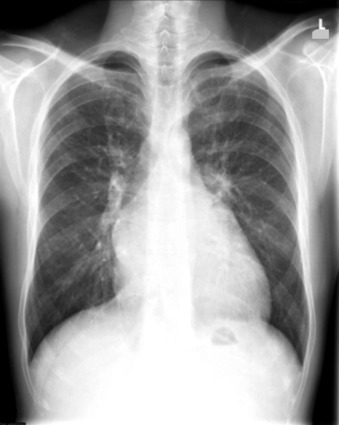

The radiographic findings of mitral stenosis ( Graphic 15-1 ; Figs. 15-1 to 15-16 ) reflect the pressure overload of the left atrium and pulmonary veins, and later of the right heart. As well, the commonly associated chronic atrial fibrillation contributes to (bi)atrial dilation. Associated rheumatic valvular lesions such as mitral regurgitation, tricuspid regurgitation, aortic insufficiency, and aortic stenosis/aortic insufficiency are common, and they alter the appearance of the heart.